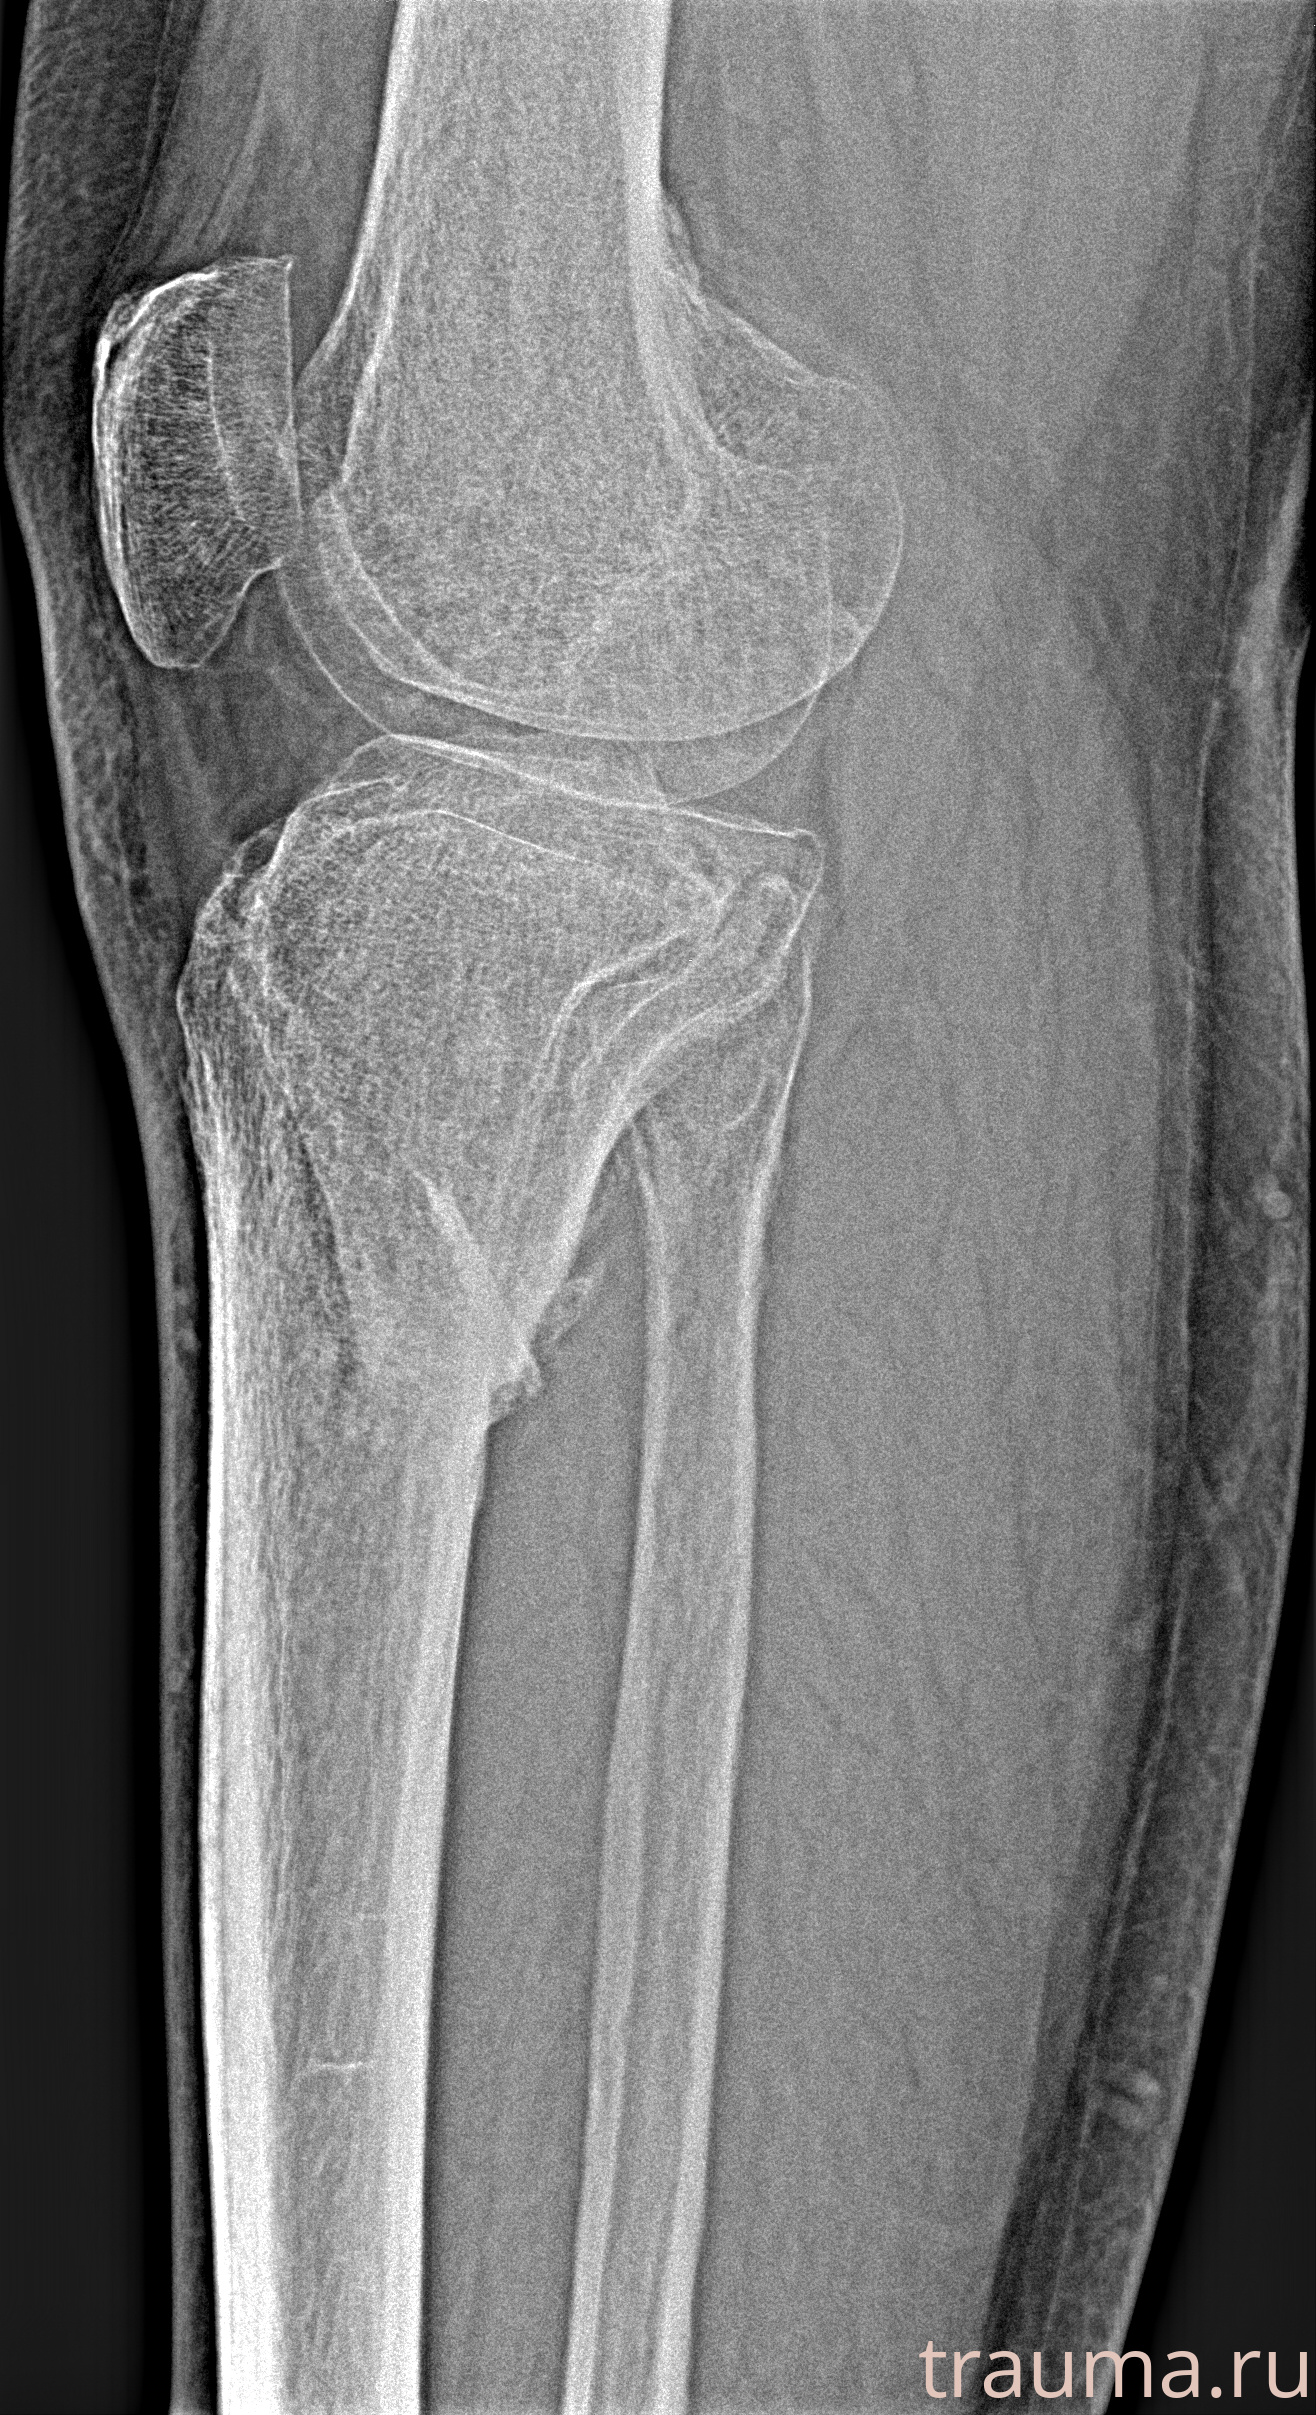

Рентгенограммы

Рентген на дому: по вашему адресу приезжает врач-рентгенолог, травматолог-ортопед с мобильным рентгеновским аппаратом, проводит диагностику травмы или заболевания, делает необходимые рентгенограммы, дает рекомендации по дальнейшему лечению. Получить качественные снимки в домашних условиях возможно благодаря уникальной методике, разработанной МосРентген Центром для института  Склифосовского